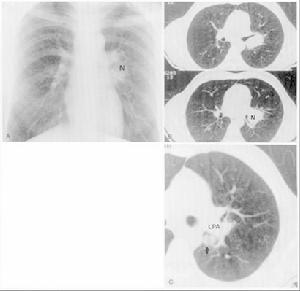

2.X線、CT檢查除外結核及腫瘤占位性病變。

實驗檢查

組織細胞壞死性淋巴結炎所有患者外周血白細胞(1.4~8.1)×109/L(除4例外,其餘均<4×109/L),13例淋巴細胞比例升高,1例可見5%異型淋巴細胞,15例血紅蛋白降低。25例血沉升高(23~61mm/h),10例血乳酸脫氫酶(LDH)升高(480~660IU/L)。19例丙氨酸氨基轉移酶(ALT)、門冬氨酸氨基轉移酶(AST)升高。2例鹼性磷酸酶(ALP)輕度升高。EB病毒抗體IgA陽性1例,IgM陽性3例,IgG陽性2例,巨細胞病毒抗體IgG陽性5例,單純皰疹病毒抗體IgG陽性2例,柯薩奇病毒抗體系列均陰性。1例抗核抗體陽性,結核抗體及結核菌素試驗均為陰性。1例X線片顯示肺門淋巴結腫大,3例B超顯示腹膜後淋巴結腫大。28例行血肥達氏反應及血培養檢查均陰性。22例行骨髓細胞學檢查,6例骨髓象感染,4例紅系增生減低,3例全血增生減低,1例中性桿狀核升高,輕度核左移,其餘正常。